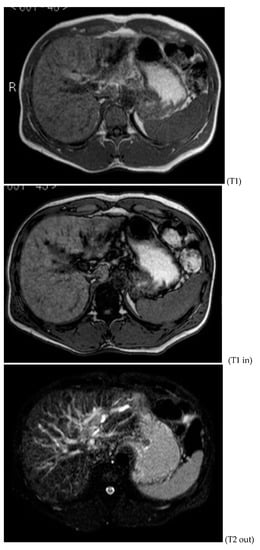

Figure 4.

MRI T1, T1 in, T1 out, and DWI.

Figure 5.

MRI T2.

A mass of 1.8 cm was detected within the biliary branch for the third hepatic segment, characterized by nodular impregnation in the arterial phase and irregular and partial washout in the portal venous phase. These findings were compatible with a heterologous lesion, although it was not possible to perform a diagnosis among HCC, intrahepatic CCA or other pathological lesions.